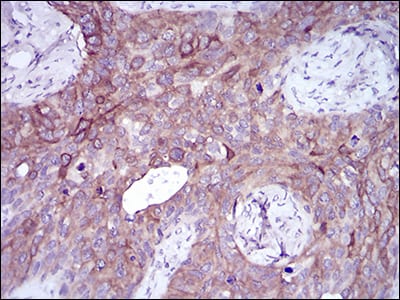

Immunohistochemical analysis of paraffin-embedded human cervical cancer tissues using SNAI2 mouse mAb with DAB staining.

Immunohistochemical analysis of paraffin-embedded human colon cancer tissues using SNAI2 mouse mAb with DAB staining.